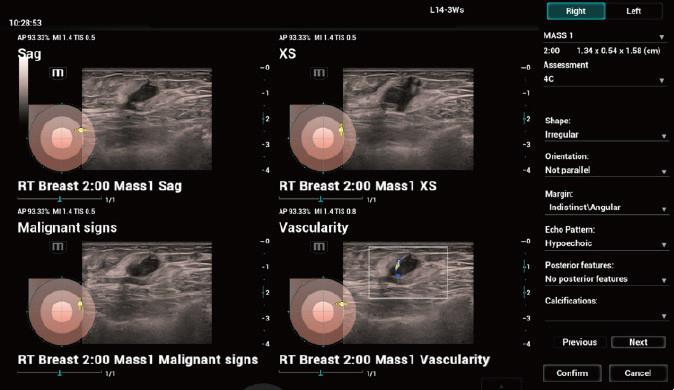

3、Smart Breast乳腺病灶自動分析

提供基于BI-RADS的乳腺病灶自動分析,包括自動病灶識別、測量、注釋、分析及報(bào)告等,以病灶為中心,提供標(biāo)準(zhǔn)化的掃描流程指引。全面完善的多病灶多切面綜合管理及分析,可進(jìn)一步提升診斷信息維度及準(zhǔn)確率。